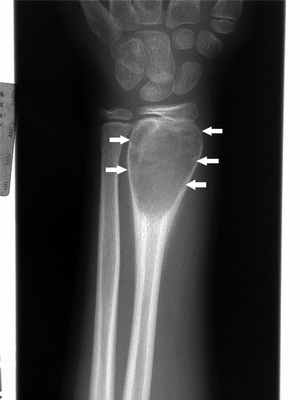

Остеоид-остеома. Одни авторы рассматривают остеоид-остеому как хронический очагово-некротический негнойный остеомиелит, другие относят остеоид-остеому к опухолям • Частота. Остеоид-остеому выявляют у лиц молодого возраста (11–20 лет), мужчины болеют в 2 раза чаще. Обычно остеоид-остеома — солитарная опухоль, локализующаяся в любом отделе скелета (чаще в длинных трубчатых костях). На первом месте по частоте поражения стоит бедренная кость, затем большеберцовая и плечевая кости • Клиническая картина. Боли, особенно по ночам, локализованные, усиливающиеся при надавливании на очаг. Кожные покровы без изменений. При локализации опухоли на нижних конечностях — хромота. Рентгенографически выявляют очаг деструкции костной ткани овальной формы с чёткими контурами. Вокруг очага — зона остеосклероза за счёт периостальных и в меньшей степени эндостальных изменений. Для уточнения характера поражения и более чёткого выявления очага показана КТ. Дифференциальную диагностику при остеоид-остеоме проводят с костным абсцессом Броди • Лечение хирургическое. После радикального удаления, как правило, остеоид-остеома не рецидивирует.

35. Остеоид-остеома

Частота - 4 - 10%

Поражаемый возраст 20-30 лет.

Излюбленная

локализация большеберцовая и

малоберцовая кости,

задние элементы

позвонков.

Клиника – интенсивные

ночные боли.36. Остеоид-остеома

37. Особая примета

Главный рентгеновский признак –

мелкий (диаметром несколько мм)

участок деструкции, который окружен

выраженным склеротическим

процессом.

Остеоидная остеома

Остеоидостеома чаще всего встречается в молодом возрасте (обычно от 10 до 35 лет) в длинных костях, но может возникать в любой кости скелета. Характерны боли (обычно усиливающиеся по ночам, отражающие ночное усиление воспалительных изменений, опосредованных простагландинами). Боли купируются при приеме слабых анальгетиков (в частности, аспирина и других нестероидных противовоспалительных препаратов (НПВП), подавляющих выработку простагландинов. У растущих детей воспалительные изменения и ассоциированная гиперемия, локализующиеся вблизи открытой зоны роста, могут индуцировать избыточный рост и несоответствие длины конечностей. Во время осмотра можно наблюдать атрофию региональных мышц, поскольку боль обусловливает снижение физической активности.

При использовании методов визуализации выявляют типичные изменения: небольшая зона просветления, окруженная широкой склеротической каймой. При подозрении на наличие опухоли следует выполнить сцинтиграфию всего тела с технецием-99m, при которой остеоидостеома характеризуется повышенным накоплением изотопа, несмотря на то, что многие другие костные поражения проявляются также. Выполняют также КТ или МРТ, которые являются наиболее информативными диагностическими методами. Обычная пленка или тонкосрезный КТ-скан позволяют увидеть классический симптом "бычьего глаза" в месте расположения истинного очага опухоли, окруженного зоной реактивного костеобразования.